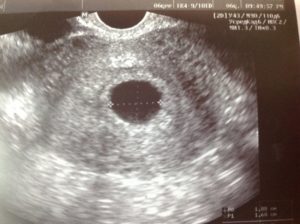

Во время ультразвукового исследования врач может обнаружить замершую беременность. Этот метод считается «золотым» стандартом при диагностике данной патологии. Отсутствие сердцебиений и отставание плода в размерах – главные симптомы замершей беременности при УЗИ.

• УЗИ: покажет прекращение сердцебиения плода. Не паникуйте раньше времени, если врач не услышал сердцебиение плода через стетоскоп — такое возможно при переднем расположении плаценты или наличии жировой прослойки на брюшной стенке;